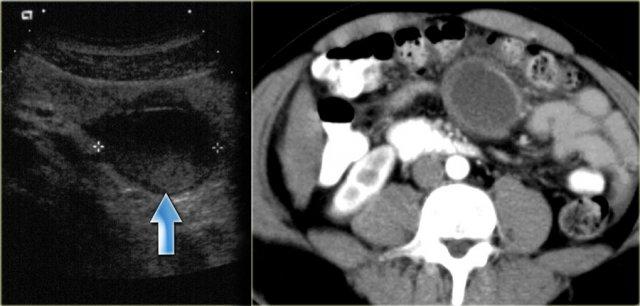

Nang Giả Không Do Tụy

Nang giả không do tụy là di tích của một khối máu tụ hoặc ổ nhiễm trùng cũ.

Hầu hết các bệnh nhân này có tiền sử chấn thương bụng trước đó.

Thường có thành dày và có thể có cặn lắng bên trong tổn thương.

Bệnh nhân bên trái đã bị tai nạn xe hơi tám tháng trước.

Đây có thể là khối máu tụ mạc treo cũ do chấn thương dây an toàn.

Lưu ý thành dày trên CT và cặn lắng trên siêu âm.

Bên trái là hình ảnh bệnh phẩm và CT của một nang giả không do tụy.

Lưu ý thành dày.

Đây có thể là khối máu tụ hoặc áp xe cũ.

Có thể gợi ý chẩn đoán này khi có tiền sử dương tính và thấy thành dày hoặc cặn lắng.